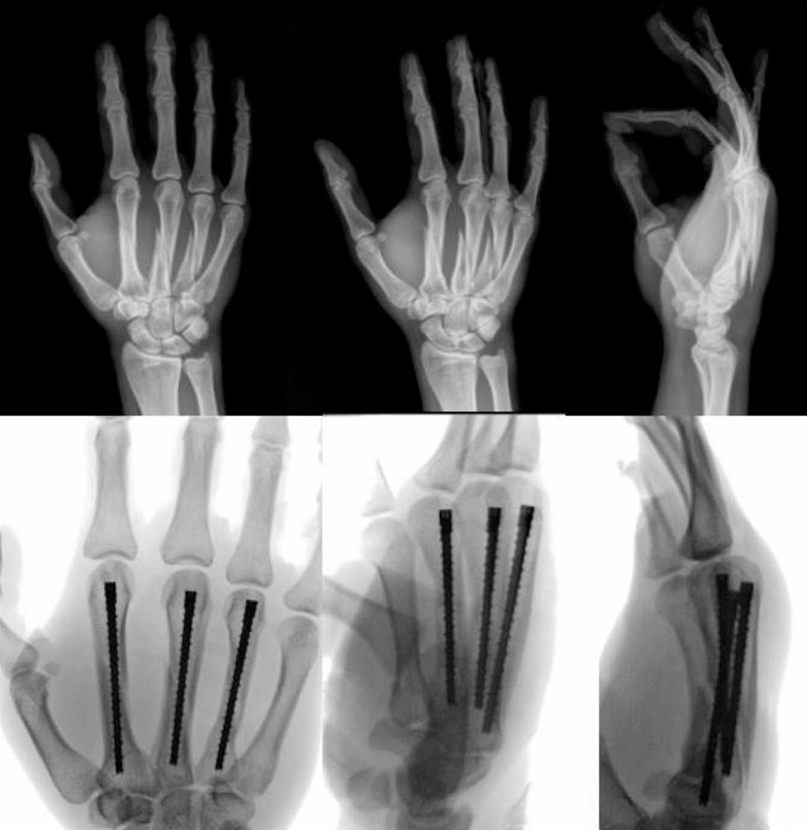

5. Intramedullary Screw Fixation for Metacarpal Neck Fractures

6. Intramedullary Screw Fixation for Multiple Spiral Metacarpal Shaft Fractures

Intramedullary Screw Fixation.png